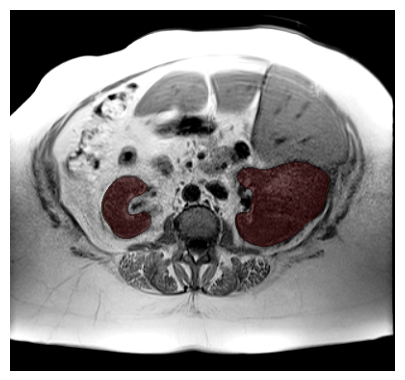

Purpose: To introduce a deep learning model capable of multi-organ segmentation in MRI scans, offering a solution to the current limitations in MRI analysis due to challenges in resolution, standardized intensity values, and variability in sequences. Materials and Methods: he model was trained on 1,200 manually annotated MRI scans from the UK Biobank, 221 in-house MRI scans and 1228 CT scans, leveraging cross-modality transfer learning from CT segmentation models. A human-in-the-loop annotation workflow was employed to efficiently create high-quality segmentations. The model's performance was evaluated on NAKO and the AMOS22 dataset containing 600 and 60 MRI examinations. Dice Similarity Coefficient (DSC) and Hausdorff Distance (HD) was used to assess segmentation accuracy. The model will be open sourced. Results: The model showcased high accuracy in segmenting well-defined organs, achieving Dice Similarity Coefficient (DSC) scores of 0.97 for the right and left lungs, and 0.95 for the heart. It also demonstrated robustness in organs like the liver (DSC: 0.96) and kidneys (DSC: 0.95 left, 0.95 right), which present more variability. However, segmentation of smaller and complex structures such as the portal and splenic veins (DSC: 0.54) and adrenal glands (DSC: 0.65 left, 0.61 right) revealed the need for further model optimization. Conclusion: The proposed model is a robust, tool for accurate segmentation of 40 anatomical structures in MRI and CT images. By leveraging cross-modality learning and interactive annotation, the model achieves strong performance and generalizability across diverse datasets, making it a valuable resource for researchers and clinicians. It is open source and can be downloaded from https://github.com/hhaentze/MRSegmentator.